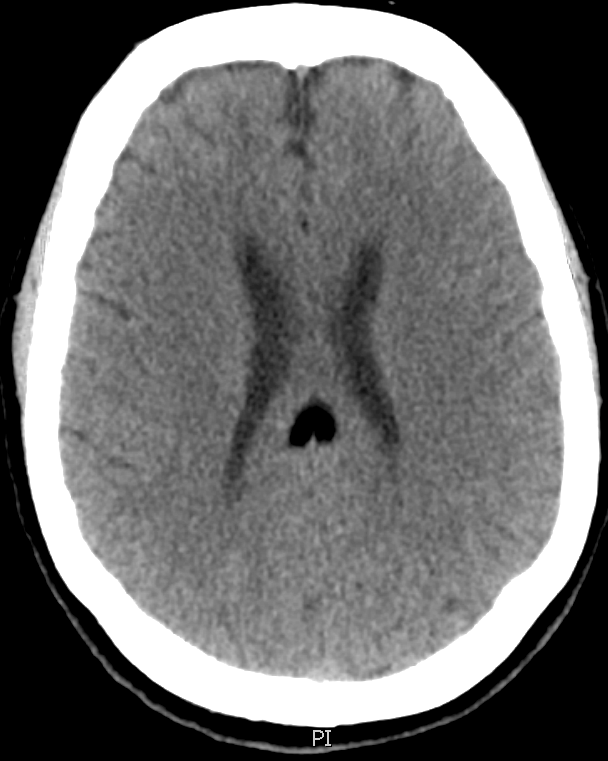

A middle aged woman was seen in the emergency department for confusion, and a non-enhanced head CT was obtained, shown below. Her exam was otherwise normal.

All three images above are non-enhanced head CT’s. First, locate the lesion – it is highlighted by a green arrow in the saggital, and by a blue arrow with bone windowing in the axial imaging. Where is it? What is the density compared to the surrounding brain tissue and CSF? Given the density, what should be in your differential diagnosis?

The answer is B) this is a lipoma. Only fat and air have a density below that of CSF on head CT. Although both lipomas and free air can look similar on normal brain windowing, by adjusting the image settings to bone windowing (middle image with blue arrow above), you will see that the lipoma is no longer totally dark.

Lipomas are relatively common, benign fatty tumors. They tend to be in the midline, just like this one is. They are usually developmental and rarely cause problems later in life – most of the time they are incidental findings like in this case. If large, they can disrupt the development of midline structures like the corpus callosum.